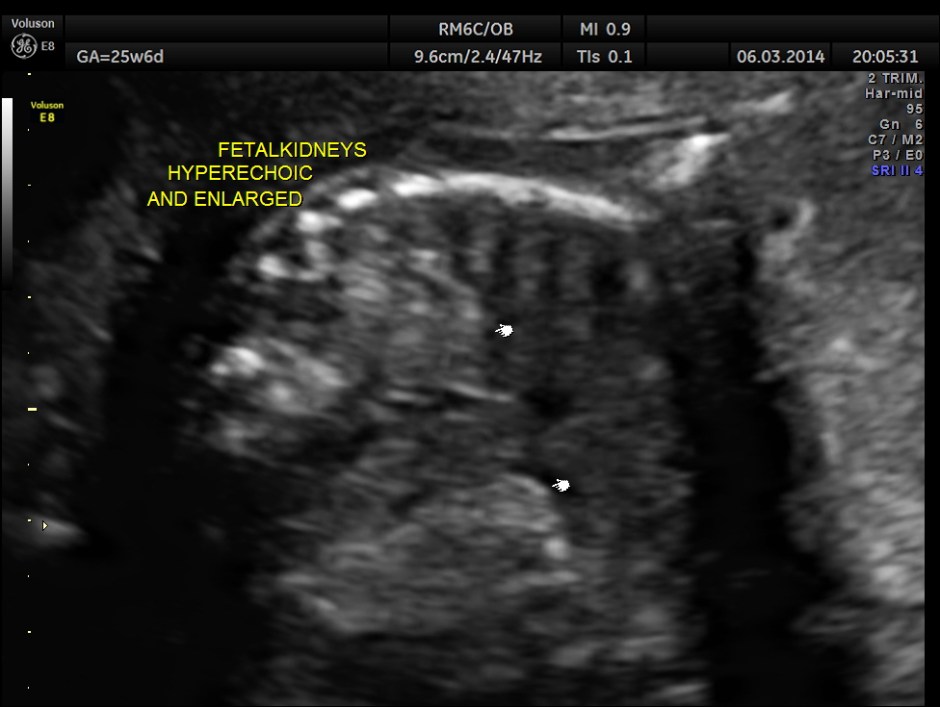

Fetal kidneys are hyperechoic and enlarged.